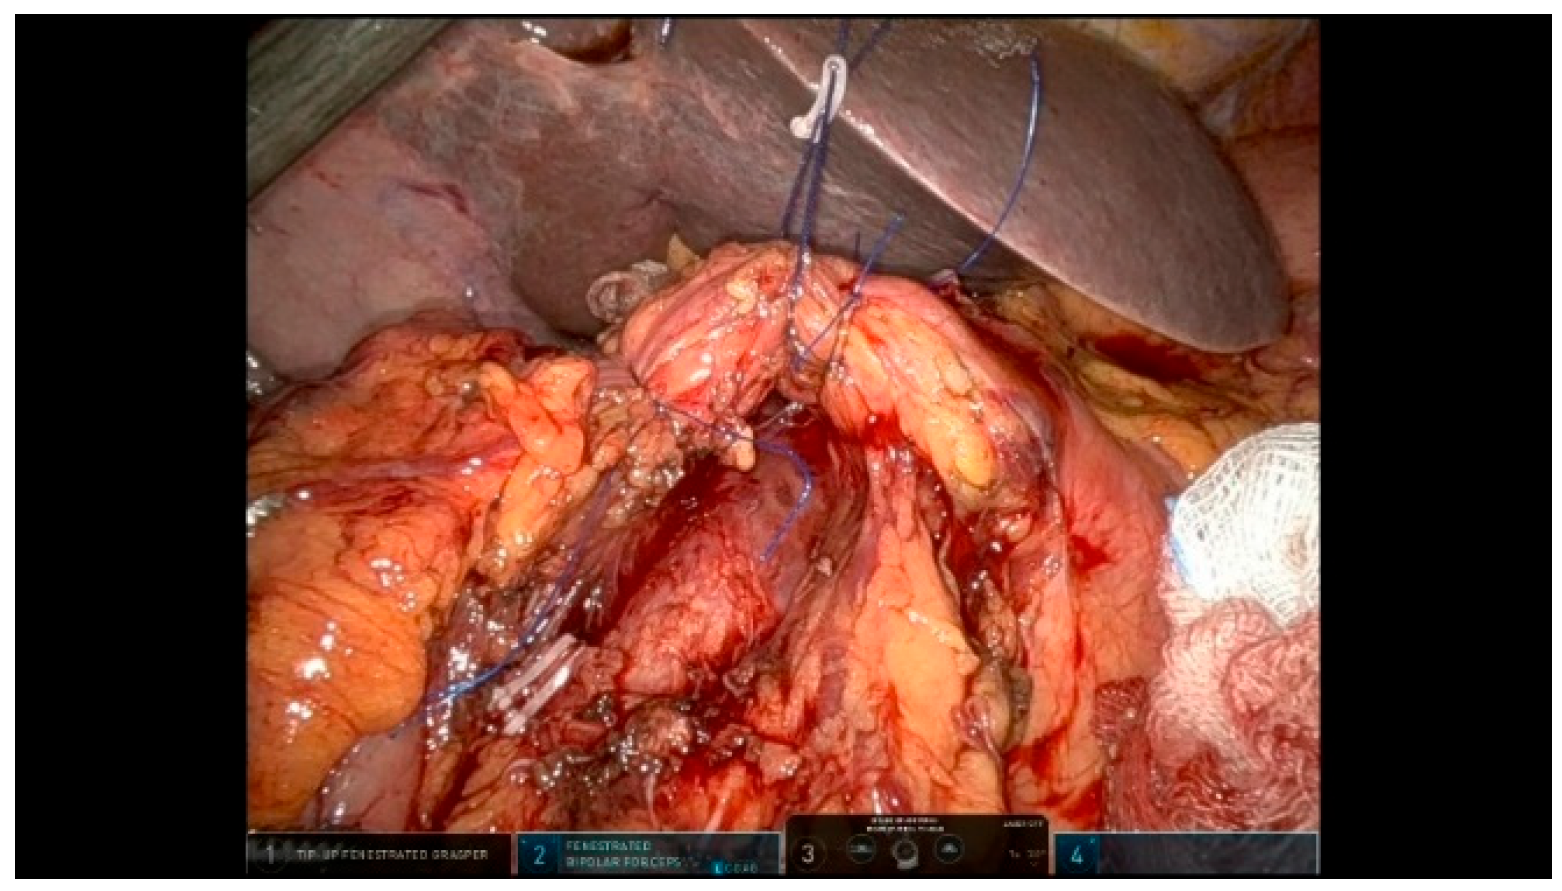

3.2.1. Step 11: Pancreaticojejunostomy